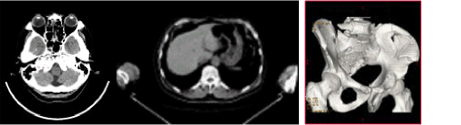

当院は平成22年12月より従来のシングルX線CT装置から、2列マルチスライスCT(MDCT)を導入しました。

GE社製 New Pro SpeedU Premium

・撮影時間が従来のCTより半分に短縮

・患者様の症状、状態をより考慮した撮影が可能

・腕上げ不可、息止め不可の患者様でも撮影が可能

・従来CTより高画質になり、診断能が向上